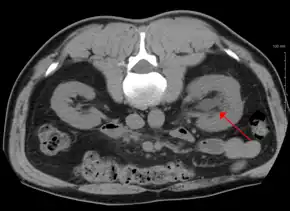

Hydronephrosis due to a kidney stone at the ureteral vesicular junction seen on CT scan

Imaging studies, such as an intravenous urogram (IVU), renal ultrasonography, CT, or MRI, are also important investigations in determining the presence and/ or cause of hydronephrosis. Whilst ultrasound allows for visualisation of the ureters and kidneys (and determine the presence of hydronephrosis and / or hydroureter), an IVU is useful for assessing the anatomical location of the obstruction. Antegrade or retrograde pyelography will show similar findings to an IVU but offer a therapeutic option as well. Real-time ultrasounds and Doppler ultrasound tests in association with vascular resistance testing helps determine how a given obstruction is effecting urinary functionality in hydronephrotic patients.[11]

The choice of imaging depends on the clinical presentation (history, symptoms and examination findings). In the case of renal colic (one sided loin pain usually accompanied by a trace of blood in the urine) the initial investigation is usually a spiral or helical CT scan. This has the advantage of showing whether there is any obstruction of flow of urine causing hydronephrosis as well as demonstrating the function of the other kidney. Many stones are not visible on plain X-ray or IVU but 99% of stones are visible on CT and therefore CT is becoming a common choice of initial investigation. CT is not used however, when there is a reason to avoid radiation exposure, e.g. in pregnancy.